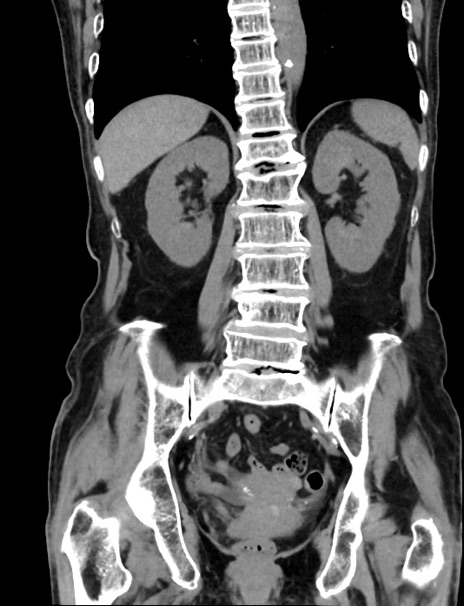

症例33(冠状断像)

【症例】70歳代 女性

【主訴】心窩部痛

【現病歴】延髄病変の精査・加療にて神経内科入院中。本日より心窩部痛あり。

【既往歴】虫垂炎

【身体所見】右下腹部を中心に圧痛と反跳痛あり。

【データ】WBC 10900、CRP 0.02